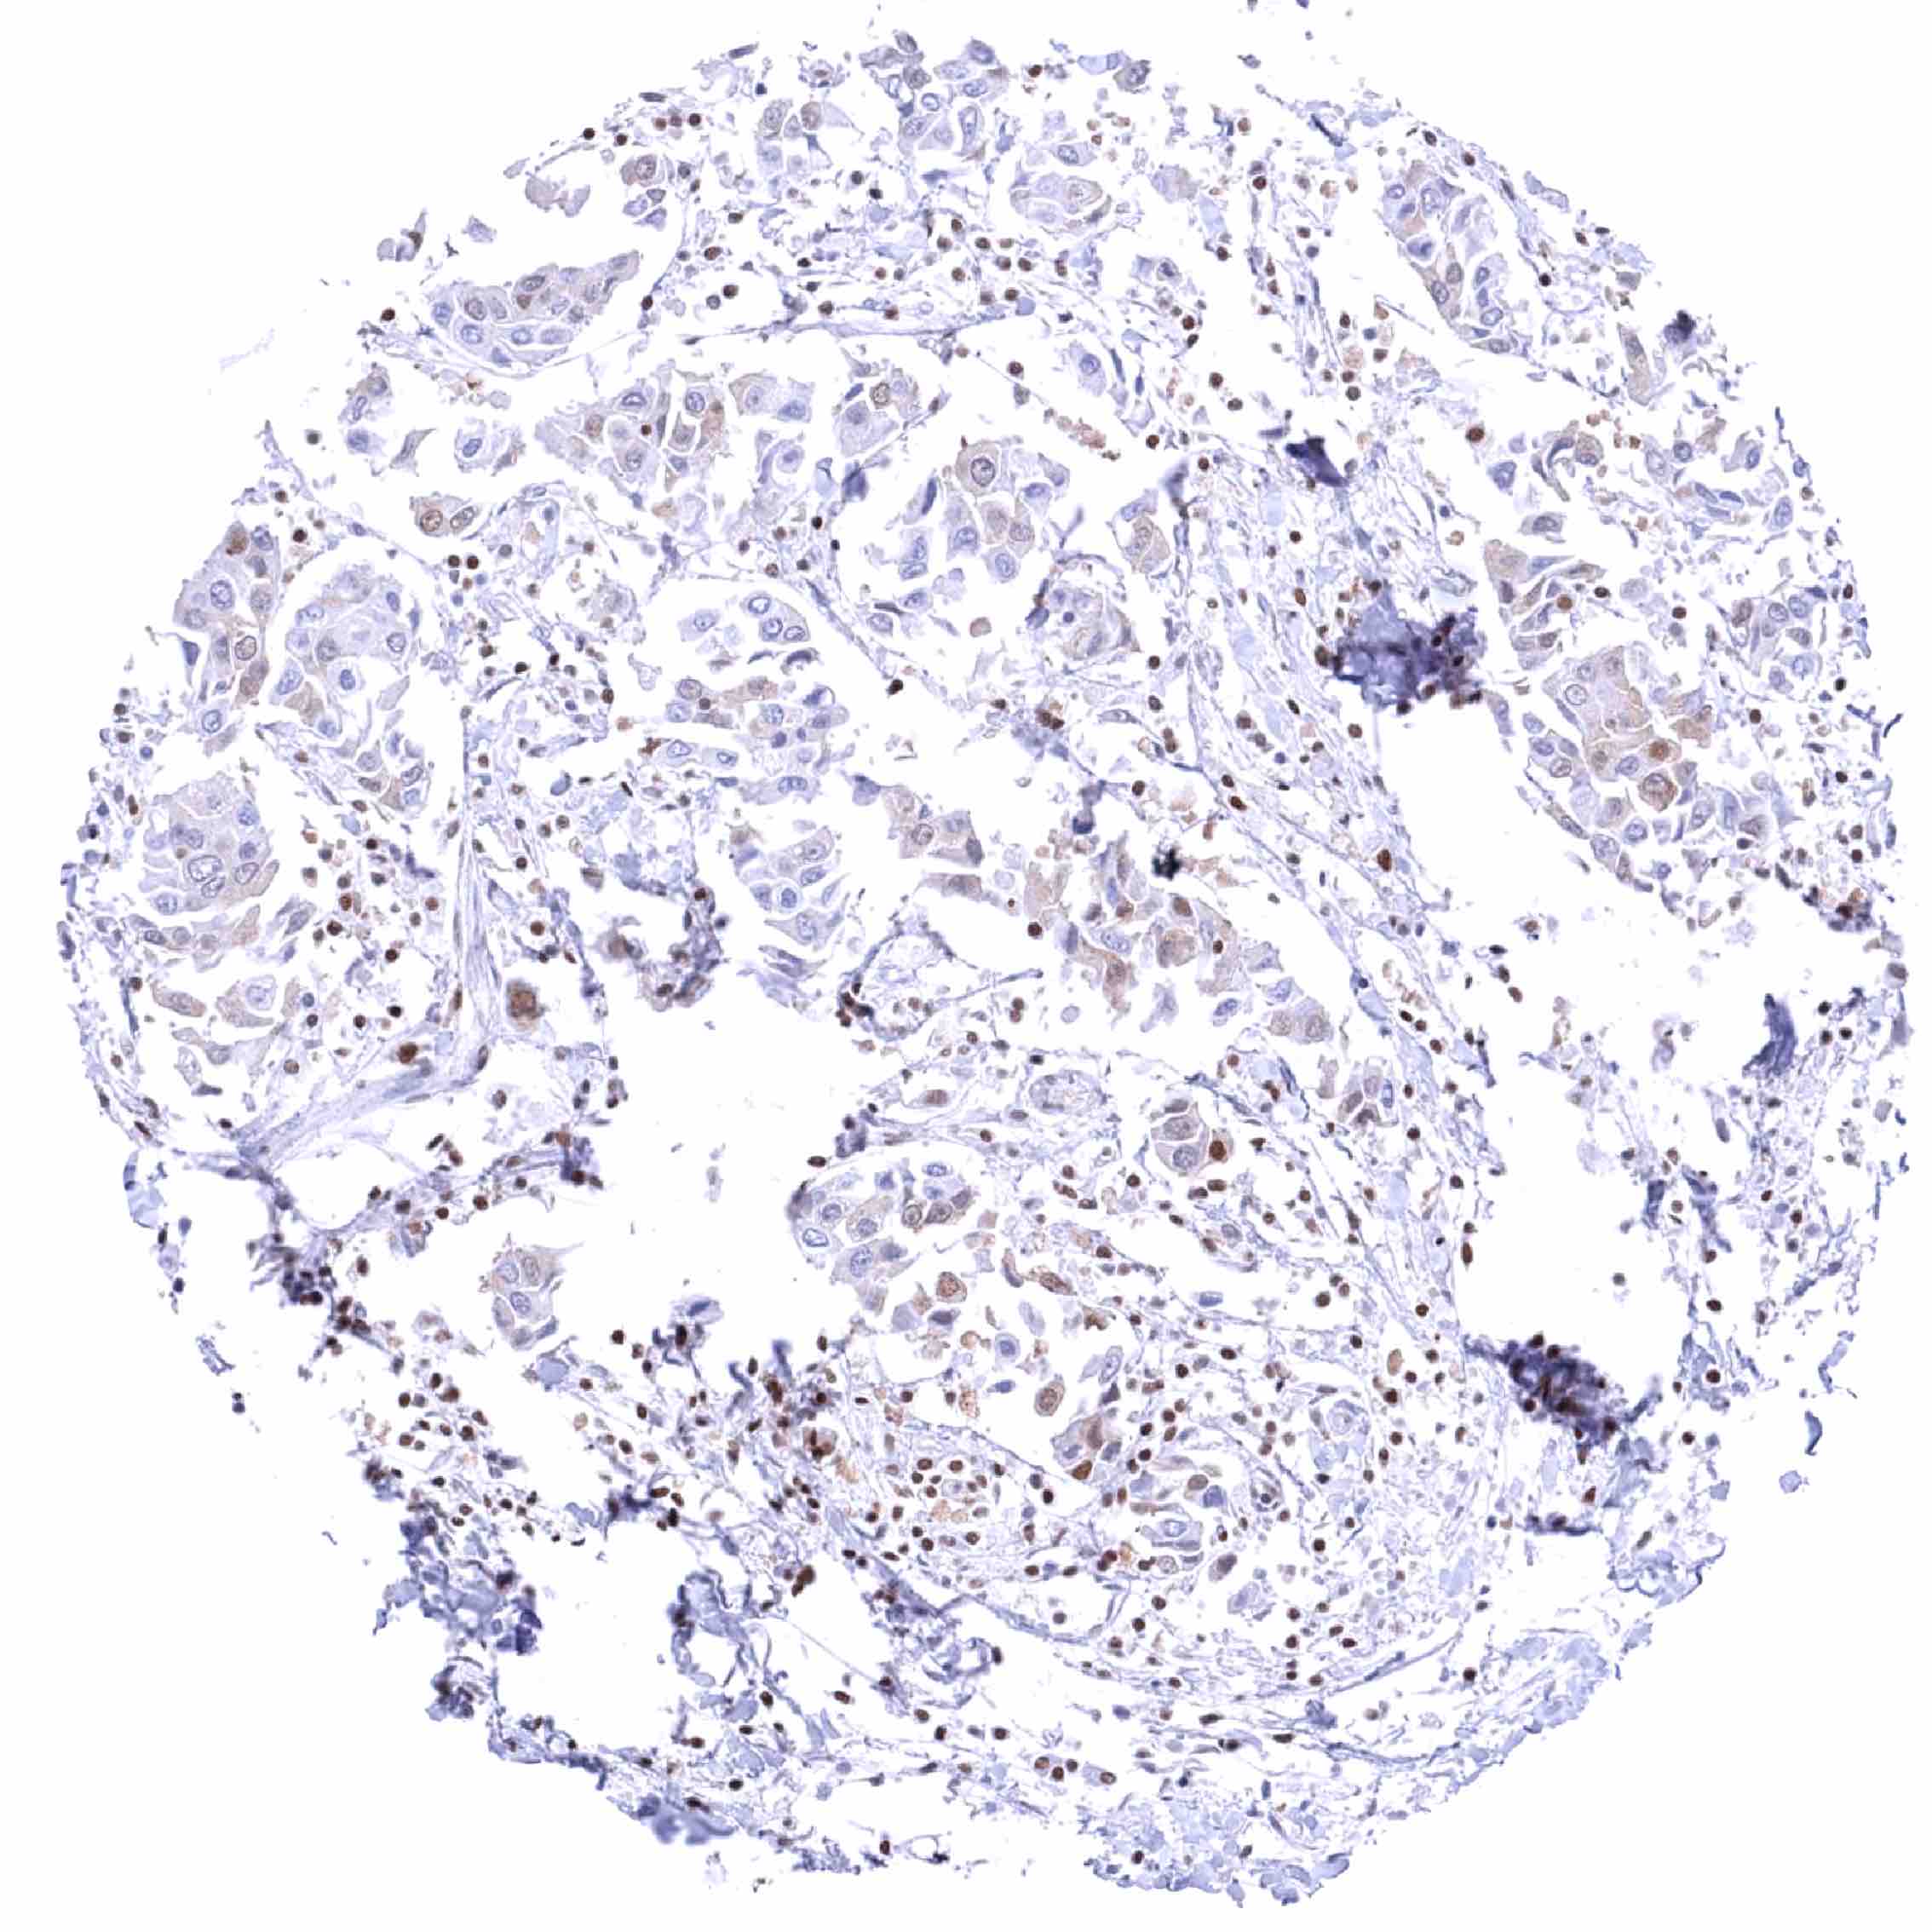

Stomach – Gastric adenocarcinoma (intestinal type) with BRD4 loss in a fraction of tumor cells. Distinct nuclear BRD4 staining of inflammatory cells.